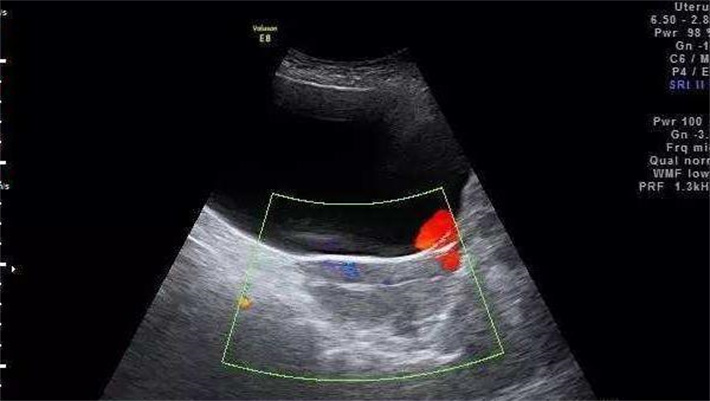

阴道超声是子宫环境检查的基础手段,其核心原理是通过高频阴道探头,直接贴近子宫,清晰显示子宫大小、形态、内膜厚度、肌层回声,以及卵巢、输卵管的基本情况,无需憋尿,能快速捕捉子宫的整体状态。